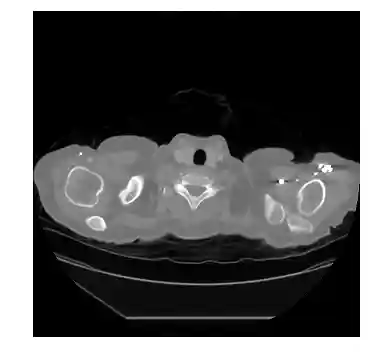

This is the codebase for performing pulmonary nodule detection and segmentation (end-to-end) using computed tomography (CT) images. Details about the methodolgy and results are in the aforementioned paper. Because of the limited space in the paper, we will elaborate the technical details here.

The detailed model architecture is demonstrated in the following figure.